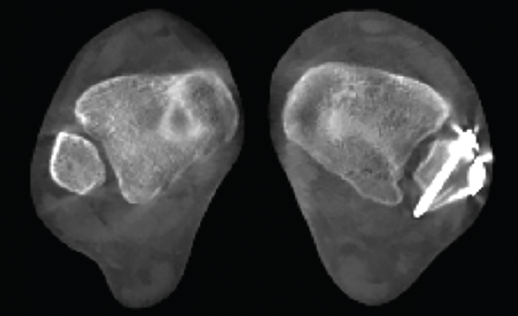

Figura 4. Estudio de la articulación subtalar bilateral.

- Patología y deformidad subtalares. Estudio de la configuración subtalar y artropatía de la misma (Figura 4).